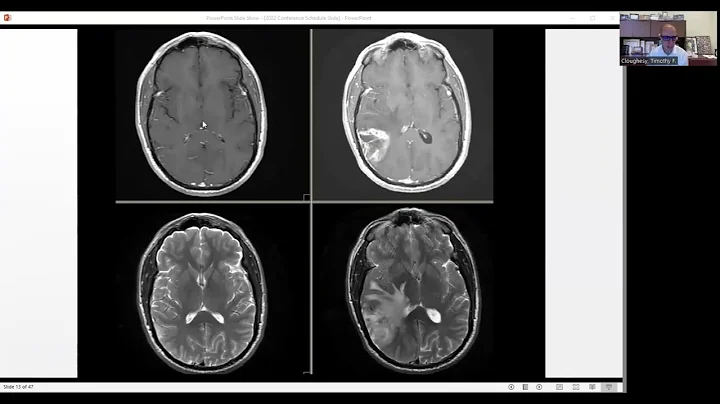

Overview Of Common Brain Tumors

Overview of Common Brain Tumors brought to you by the Medical Student Neurosurgery Training Center. Join Dr. Rupa Juthani ...